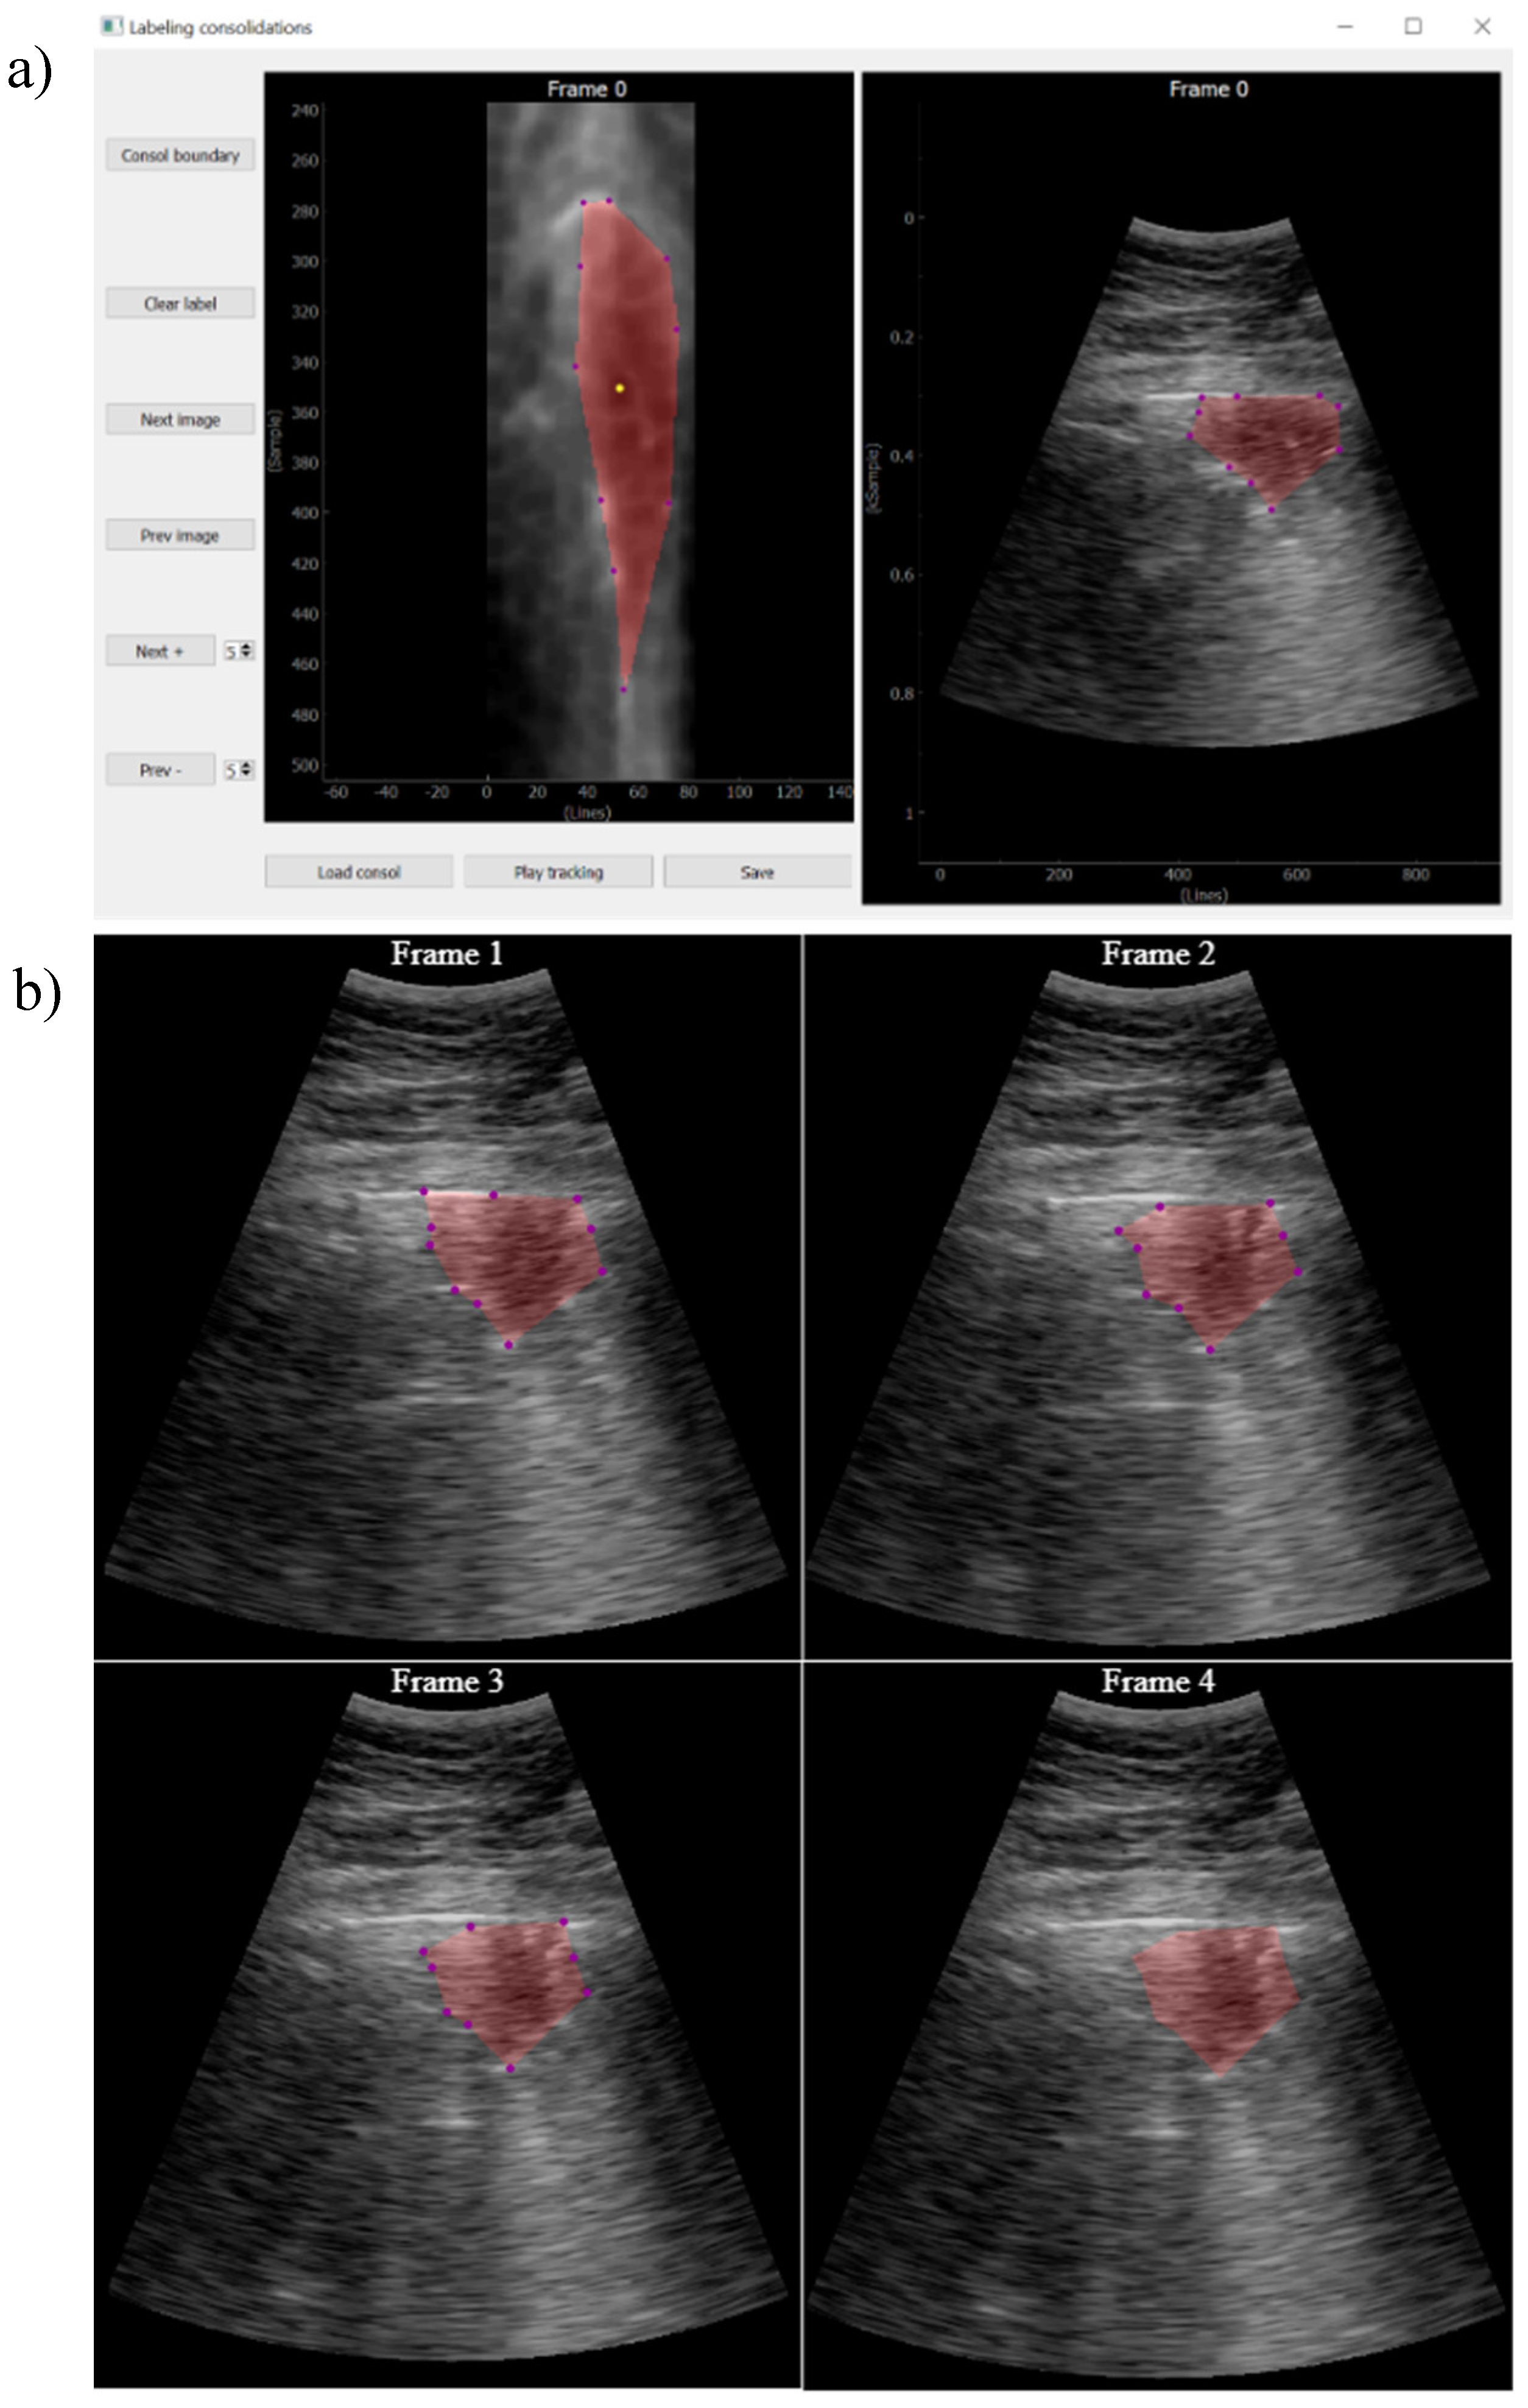

2.4.1.4. Consolidation Labelling

While pleura, A-lines and B-lines can be robustly detected by quite simple algorithms applied along each scan line, the consolidations cannot be tackled with the same approach. As they are intrinsically two-dimensional structures, it is not possible to detect them in a line-by-line basis, and image algorithms are needed.

The approach followed in this work was that, given a video labeled by the expert as containing a consolidation, a key frame where this consolidation is seen is first identified. Then, it is manually delineated using a custom developed interactive tool (Figure 6). Finally, an optical flow algorithm [23,24] tracks the movement of the consolidation in the subsequent frames, automatically generating the ground truth masks for the entire video. The optical flow algorithm is based on the principle of selecting a set of reference points and track them through the video. This algorithm is particularly suited for ultrasound images because the texture generated by the image speckle can be used for this purpose. The implemented application requests frame-by-frame validation from the user to ensure correct labelling. In case the algorithm fails in the detection, the points of interest will be re-selected again.

These semi-automatic algorithms are aimed to decrease the time required for labelling videos at frame level, while they only require manual intervention in the case of consolidations and for segmenting a unique frame. Nevertheless, because they can also fail in detecting the indications, a supervision of the whole video after it is labeled is required, with the possibility of eliminating those frames where the labeling is considered wrong.

Figure 6. a) Tool developed for consolidation annotation; b) tracking secuence over 4 consecutive frames.